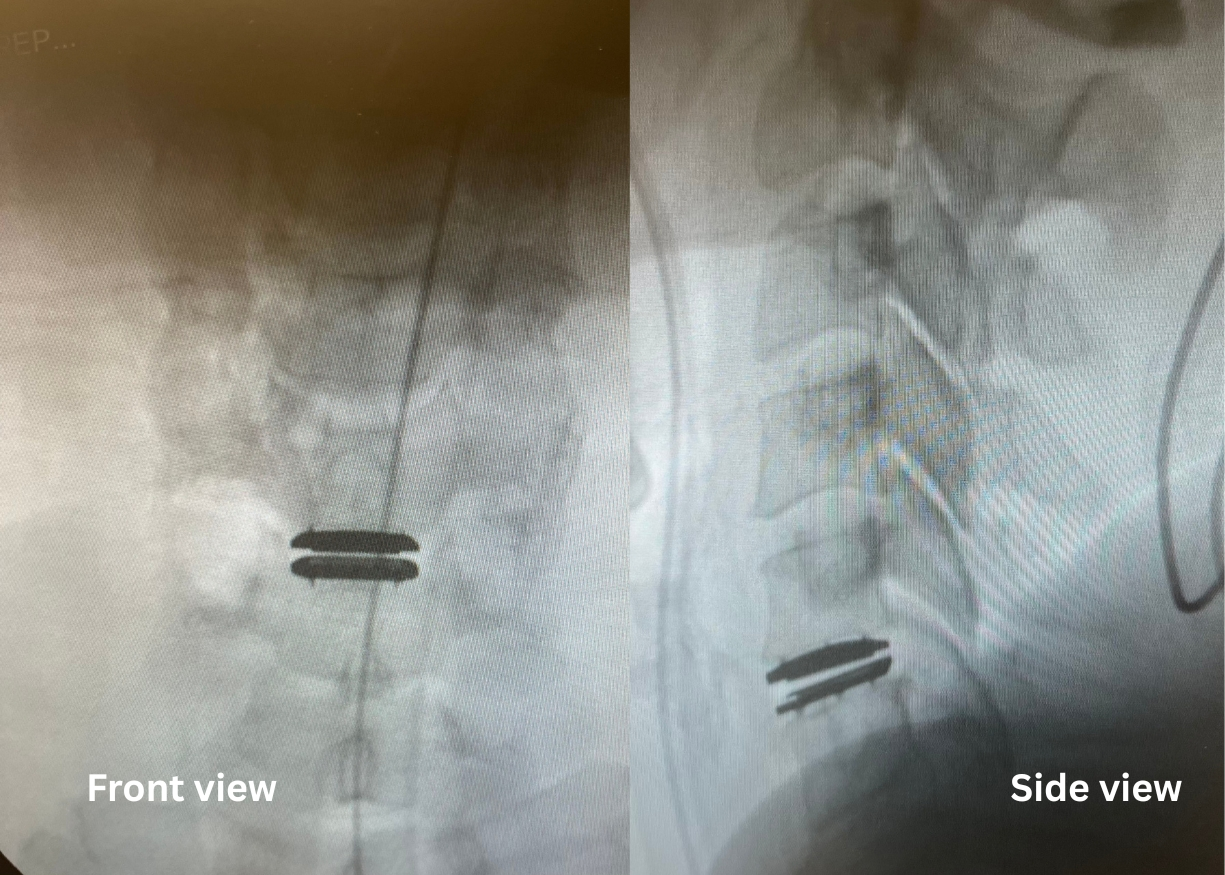

Before

Lumbar disc replacement